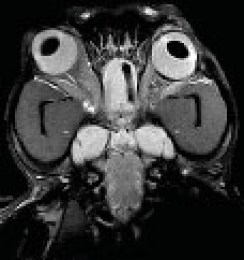

Vet-MR Grande дозволяє отримувати зображення високої якості, навіть у порівнянні з високопольними МРТ 1,5 тесла.

vet-mr-grande-2